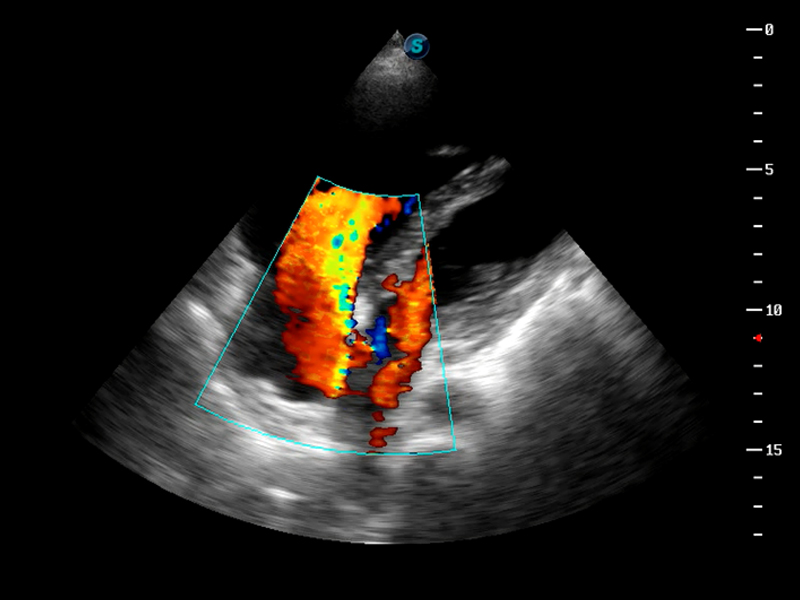

S9便携式彩色多普勒超声诊断仪是乐玩lewin国际研发的高端便携彩超设备,外观设计新颖、产品性能卓越。S9在便携超声领域采用了突破传统的触摸屏交互设计,并以先进的软件硬件技术和设计理念,为您带来清晰的图像质量、稳定的工作性能和便捷的操作体验。

TDI组织多普勒成像

AutoC智能血流追踪